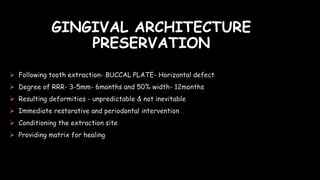

The document discusses pontic design for fixed dental prostheses. It covers pretreatment assessment of residual ridge contours, classifications of ridge deformities, surgical modification techniques, and ideal requirements for pontics. Pontic designs are classified based on their shape and materials. Factors in pontic selection include esthetics and oral hygiene. Common designs for anterior and posterior regions are described, including sanitary, ovate, and saddle pontics. Biological considerations for pontic design involve maintaining the residual ridge, abutment teeth, and supporting tissues.